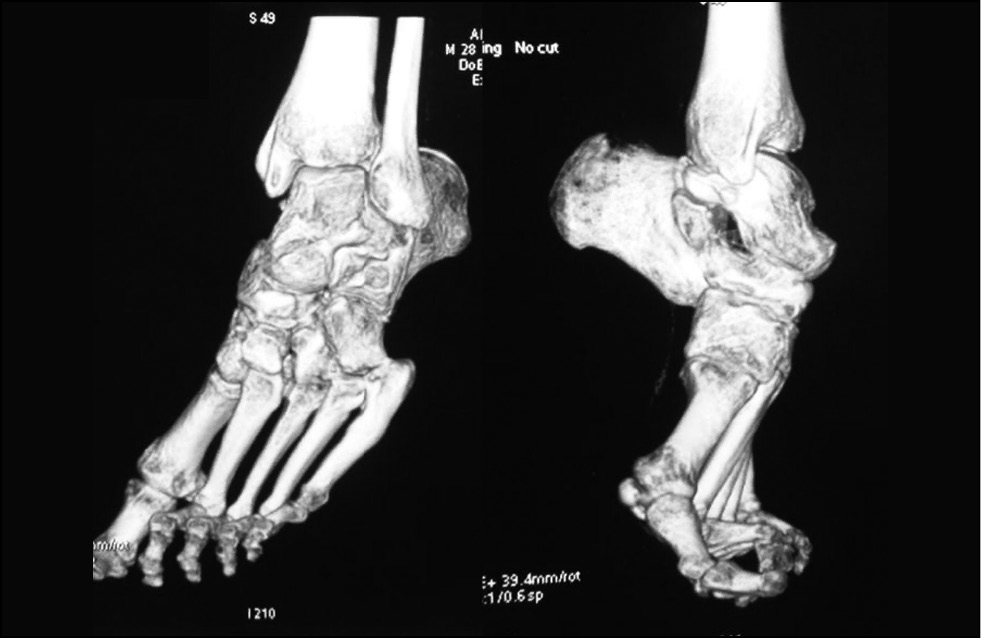

Рис. 3. Компьютерная томограмма, демонстрирующая порочную установку стоп и голеностопных суставов

Fig. 3. Computed tomogram scan demonstrating defective positioning of feet and ankle joints